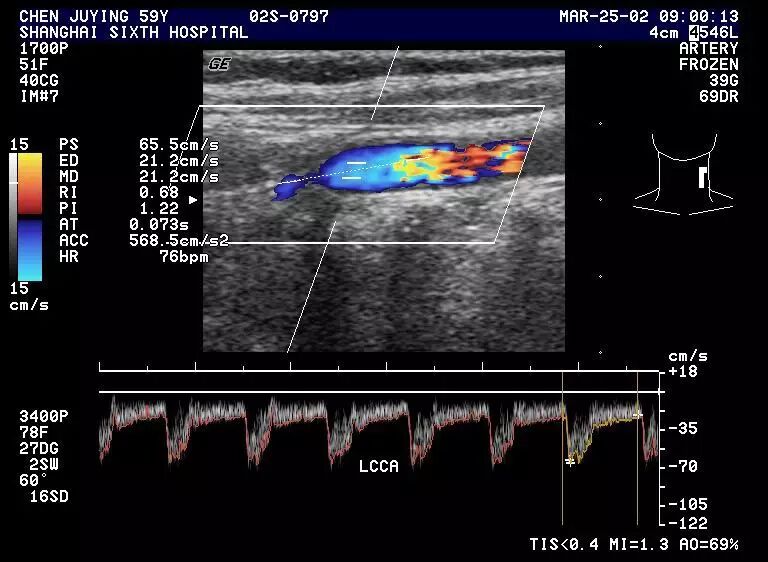

(1)正常颈总动脉血流呈三峰,收缩期有二个峰,第一峰V1大于第二峰V2,双峰间有切迹。舒张期持续低速血流,其流速介于颈内与颈外动脉之间。

1.1正常颈动脉频谱